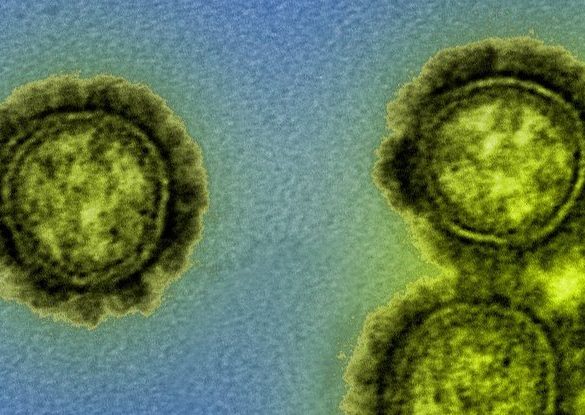

There’s been so little flu transmission during the COVID-19 pandemic that some types of flu viruses may have gone extinct, according to...

Deadly “brain-eating amoeba” infections have historically occurred in the Southern United States. But cases have been appearing farther north in...

A deadly hospital superbug has been discovered on a remote island beach, marking the first time researchers have seen this...

Scientists in California are increasingly worried about the state’s “homegrown” coronavirus variant, with studies now showing that the variant is...

The fast-spreading “UK variant” of the coronavirus could become the predominant strain in the United States by March, according to...